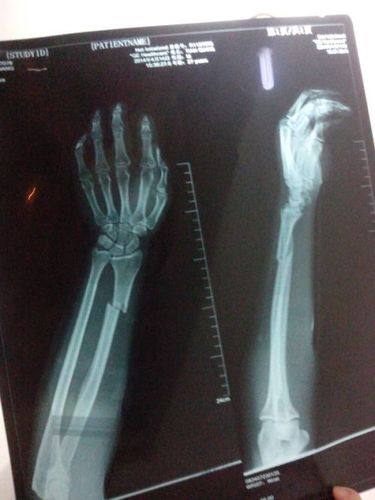

左手桡骨远端骨折图

左手桡骨远端骨折图,正常左手桡骨远端图片

患者59岁,左桡骨远端骨折,骨折断端明显

左手尺桡骨骨折图片

左手桡骨远端骨折图片

左侧桡骨远端骨折图片

桡骨远端骨折图片

左尺桡骨远端骨折图片